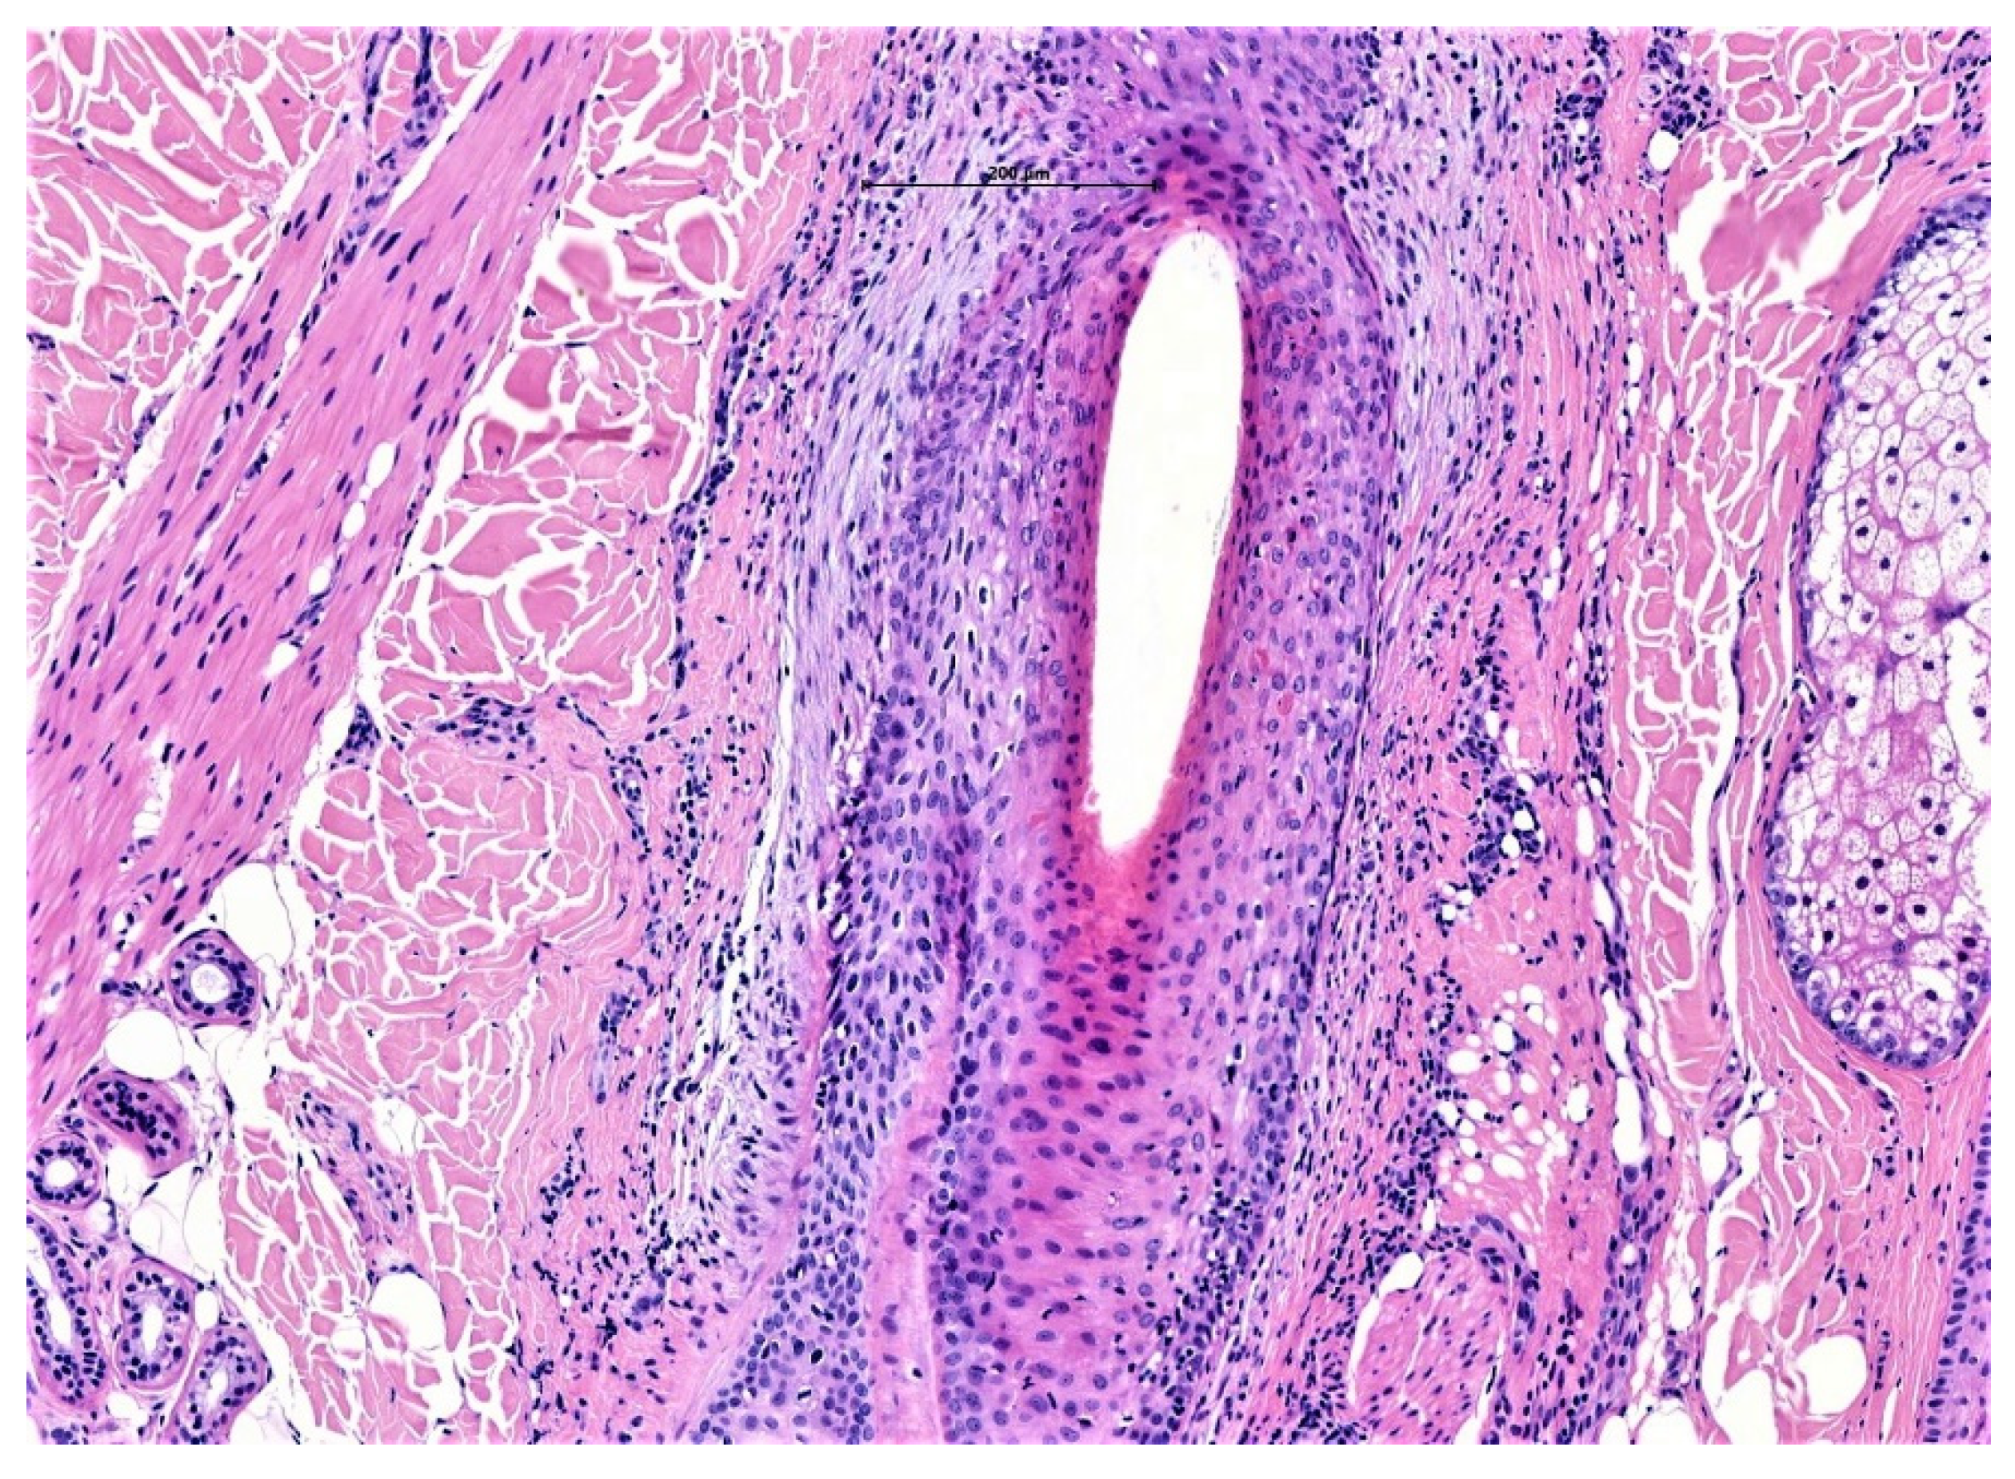

6.1. Lichen Planopilaris

- Miteva, M.; Torres, F.; Tosti, A. The ‘eyes’ or ‘goggles’ as a clue to the histopathological diagnosis of primary lymphocytic cicatricial alopecia. Br. J. Dermatol. 2012, 166, 454–455. [Google Scholar] [CrossRef] [PubMed]

- Miteva, M.; Tosti, A. The follicular triad: A pathological clue to the diagnosis of early frontal fibrosing alopecia. Br. J. Dermatol. 2012, 166, 440–442. [Google Scholar] [CrossRef] [PubMed]

| Epidermis and hair follicle epithelium | Sparing of interfollicular epidermis | Interfollicular epidermal changes (follicular plugging, vacuolar alteration and atrophy) | Eccentric atrophy of the follicular epithelium | Flattened and “squamatisation of hair follicle epithelium surrounded by a zone of fibroplasia and inflammation |

| Inflammation | Perifollicular infiltrates (predominately lymphocytic although histiocytes also occur) with sparing of deep vascular plexus and adnexal structures | Superficial and deep lymphocytic infiltrate involving eccrine glands | Variably dense lymphocytic perifollicular inflammation, primarily at the level of the upper isthmus and lower infundibulum | Predominantly neutrophils, with a component of both lymphocytes and plasma cells at varying depths |

| Distinguishing features | Peri-follicular infundibular lichenoid (band-like) inflammation and apoptotic bodies | Vacuolar interface change Dermal mucin Thickened basement membrane | PDRIS found in early disease and normal appearing scalp | Polytrichia and hair shaft granulomas as a predominant feature |